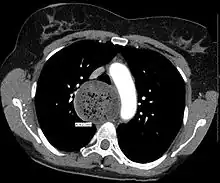

End-stage achalasia, typified by a massively dilated and tortuous oesophagus, may occur in patients previously treated but where further dilatation or myotomy fails to relieve dysphagia or prevent nutritional deterioration, and esophagectomy may be the only option.[16]

End stage disease, characterised by a markedly dilated and tortuous "burned-out" esophagus and recurrent obstructive symptoms, may require oesophageal resection in order to restore gastro-intestinal function, reverse nutritional deficits and reduce the risk of aspiration pneumonia.[17][18][19]